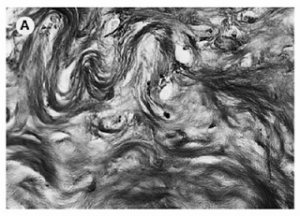

If you were to sustain a hit somewhere on your body with enough force, the point of impact would experience cell death and a micro-hemorrhage of torn capillaries. This trauma would then set up an inflammatory response in the body where vasodilation, clotting mechanisms, and white blood cells would be called upon to help the injured area. The problem is that this chemical chain of events doesn’t just “clean up” the injured area; unfortunately, it also eats/destroys the surrounding healthy tissue. So, if your injury is a small, one-time event, then it’s really no big deal, but, if it happens over and over again on a repetitive basis it becomes a real problem. The area begins to get inflamed; fibers from scar tissue cross bind to other healthy tissue and restrict freedom of motion. There is a loss of capillary beds in the tissue itself. Fluid from the inside of joint or tendon sheaths stops being produced and therefore, the sheaths lose their lubricating effect. Eventually, the healthy tissue is replaced with non-aligned, avascular tissue that has a reduced tensile strength. In other words re-injury and overuse of a joint experiencing tendonitis is likely to result in tendinosis; it’s the way the system is, unfortunately, designed.

The next treatment is very low resistance exercise to keep the joint, above and below, the injury going and the surrounding muscles pumping. This should be done with low to no resistance. The last thing that I like to do is friction massage to the injured tendon. No matter what you do, scar tissue will form secondary to the inflammatory process and we need to align the fibers (which are usually random) with the longitudinal fibers of the tendon itself for tensile strength down the road. If we don’t, a weak point will form in the tendon and, when stressed again, it will more than likely fail meaning we will start again, from the beginning. Friction massage is a “dig and roll” motion at 90 degrees, perpendicular to the long axis of the tendon working from origin to the insertion on the muscle. Start out easy and gradually, over days, increase the pressure. 3-4 x per day x 5-10 min is enough. A recap of phase one is: Fix your cause. Ice. NSAIDS, if you are able. Low-load exercise. Friction massage.